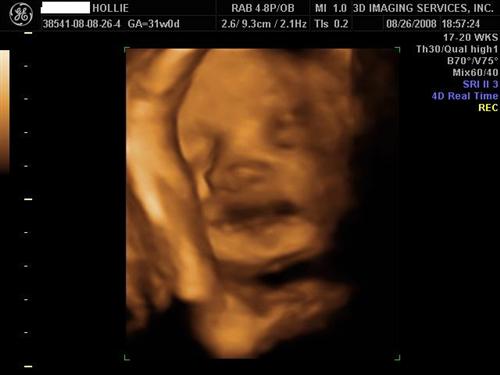

30 weeks :) super clear and adorable.

Logan's 3D pics!